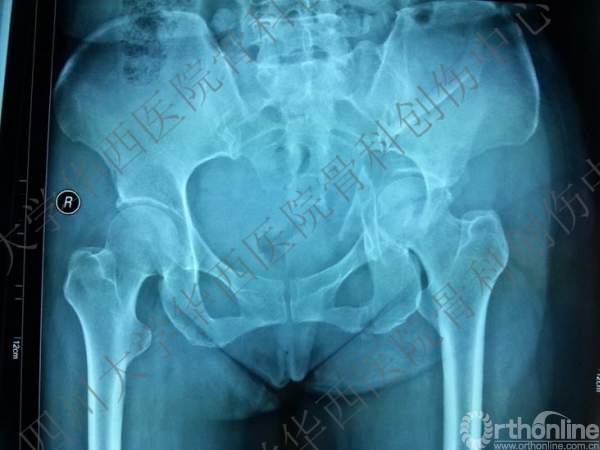

双柱骨折

基本资料: 患者,女性,45岁,车祸伤致左髋疼痛伴活动障碍5+天。患者行走时被小轿车撞伤,小轿车逃逸,被同村村民送来我院。

查体:神清合作,左髋疼痛,不能活动,足背动脉可扪及,踝关节及足趾活动正常。

诊断:左髋臼双柱骨折。